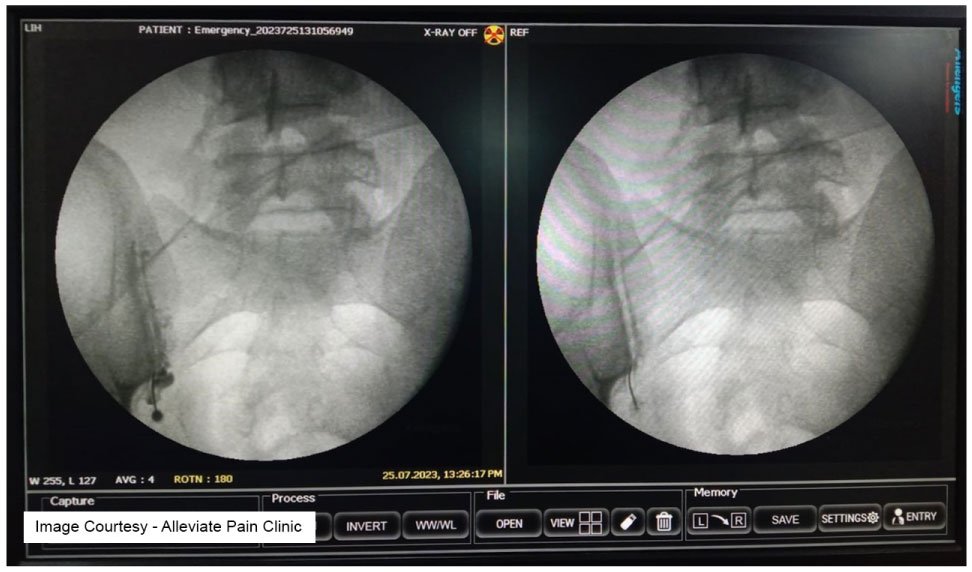

Sacroiliac Joint Injection

Cost at Alleviate Pain Clinic: Rs 25,000-45,000 (depending on the number of injections and additional services)Sacroiliac joint injections are designed to alleviate pain in the lower back and buttocks caused by sacroiliac joint dysfunction. Alleviate Pain Clinic’s competitive pricing ensures that patients can access this treatment without breaking the bank.